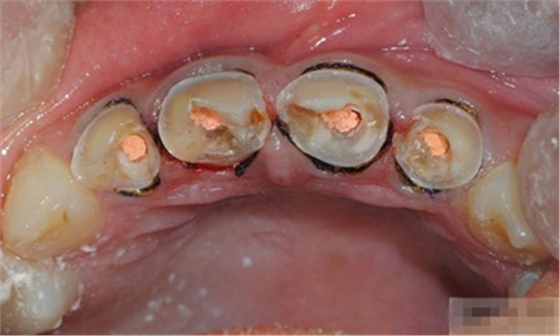

【分層堆塑】

A4本質(zhì)堆塑

Dr.Vanini建議如果牙醫(yī)選色有疑惑的話,最好應(yīng)用顏色深一些的牙本質(zhì)樹脂。

A3本質(zhì)堆塑

發(fā)育葉制作

白堊斑

切端琥珀色制作

A3頸部堆塑

涂布防氧化劑

充填初步完成